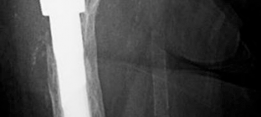

History of presenting complaint : Presents with a draining wound and well-fixed cementless components with a constrained liner due to absent abductor mechanism (Fig. 19.12). Treated with Prostalac and six weeks of IV antibiotics (Fig. 19.13). At the 6-week point, the patient sustained a ground level fall with an acetabular fracture and displacement of the acetabular Prostalac (Fig. 19.14).